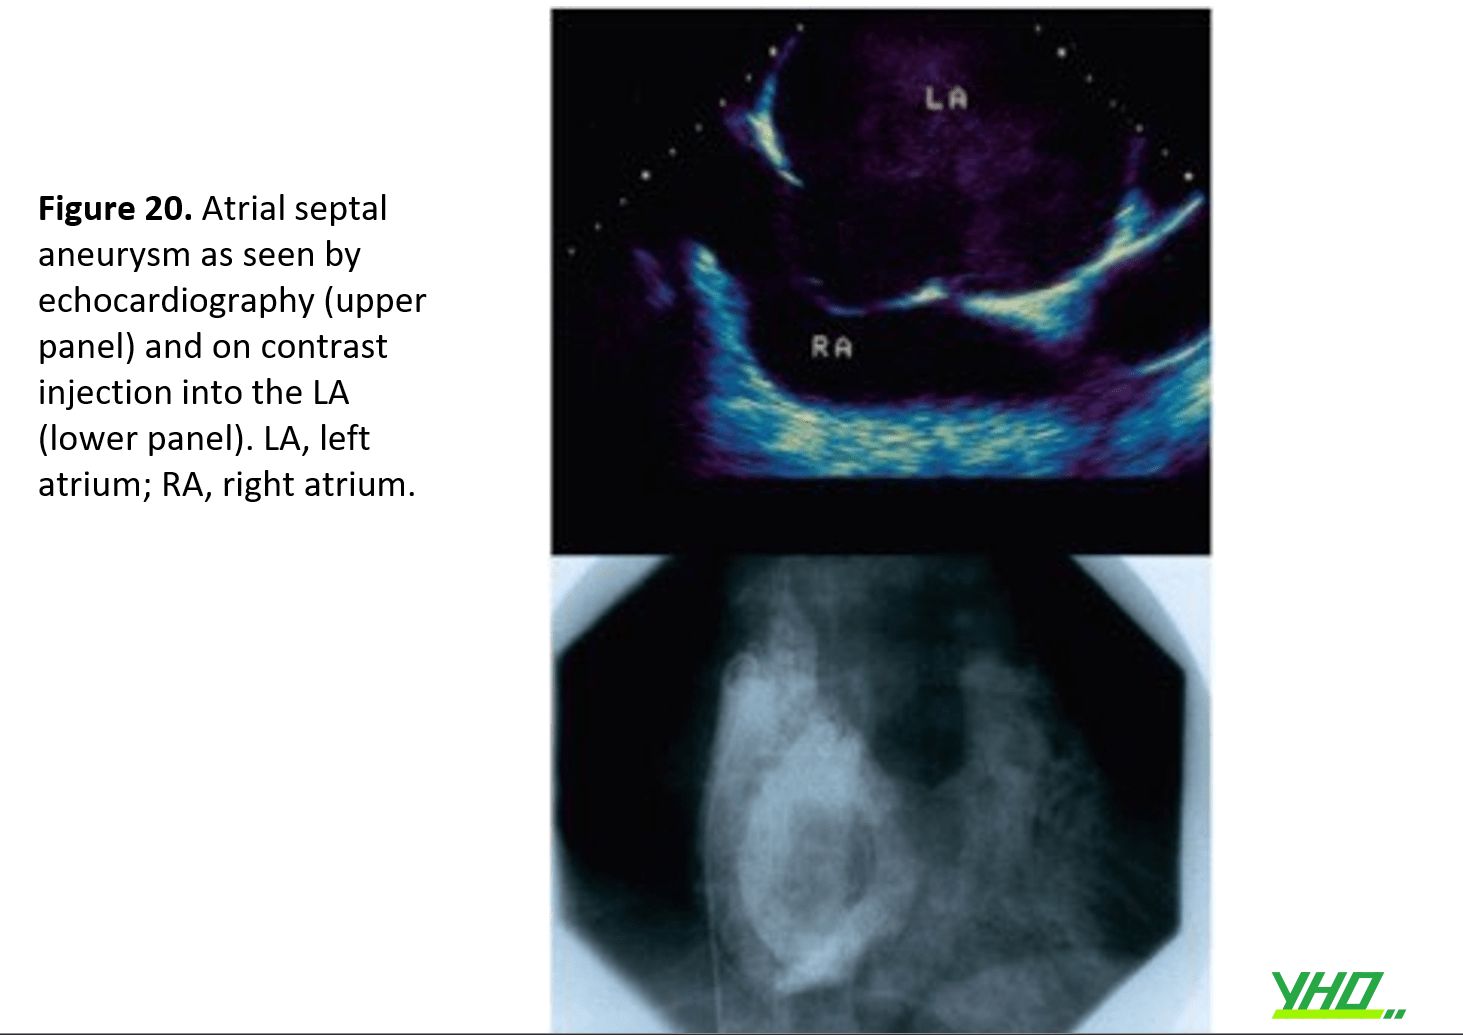

Phình vách liên nhĩ hướng vào khoang RA có thể được nhìn thấy trên TTE trước thủ thuật. Việc vượt qua có thể dễ dàng vì tỷ lệ mắc PFO cao hơn. (Figure 20) Tuy nhiên, nếu có lực cản, người thực hiện phải thận trọng để không làm thủng thành sau LA khi áp lực kim khiến túi phình sa vào nhĩ trái. Khi nghi ngờ, thành nhĩ trái sau có thể được bảo vệ bằng cách sử dụng Nitinol J-tipped SafeSept™ wire hoặc dây dẫn can thiệp đưa qua kim.